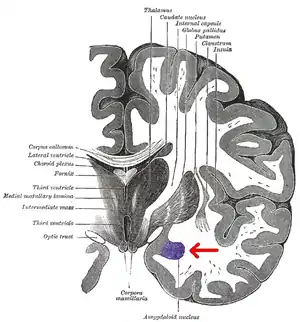

Human brain in the coronal orientation. Amygdalae are shown in dark red.

Coronal section of brain through intermediate mass of third ventricle. Amygdala is shown in purple.